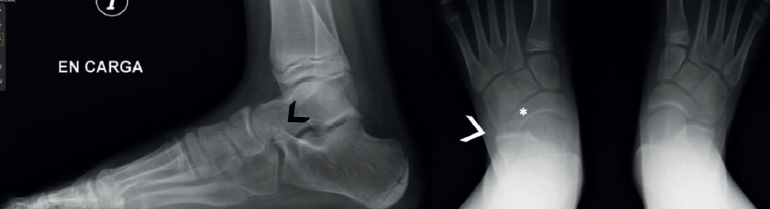

Por otro lado, debido al estudio de referencia de Harris(4), se cree que las coaliciones se asocian universalmente con la deformidad del pie plano. De este modo, todo pie plano infantil sintomático se trataría de una coalición. Sin embargo, solo alrededor de la mitad de las coaliciones se asocian con el pie plano(22) e incluso pueden asociarse con una deformidad del pie cavo(7,23,24,25) (Figura 1).

Figura 1. Paciente con coalición talocalcánea bilateral. A: pie derecho cavo-varo, sincondrosis y pie izquierdo; B: plano valgo, barra ósea; C: en la radiografía lateral izquierda se aprecia el c-sign y en la derecha se aprecia la ausencia de la faceta medial.